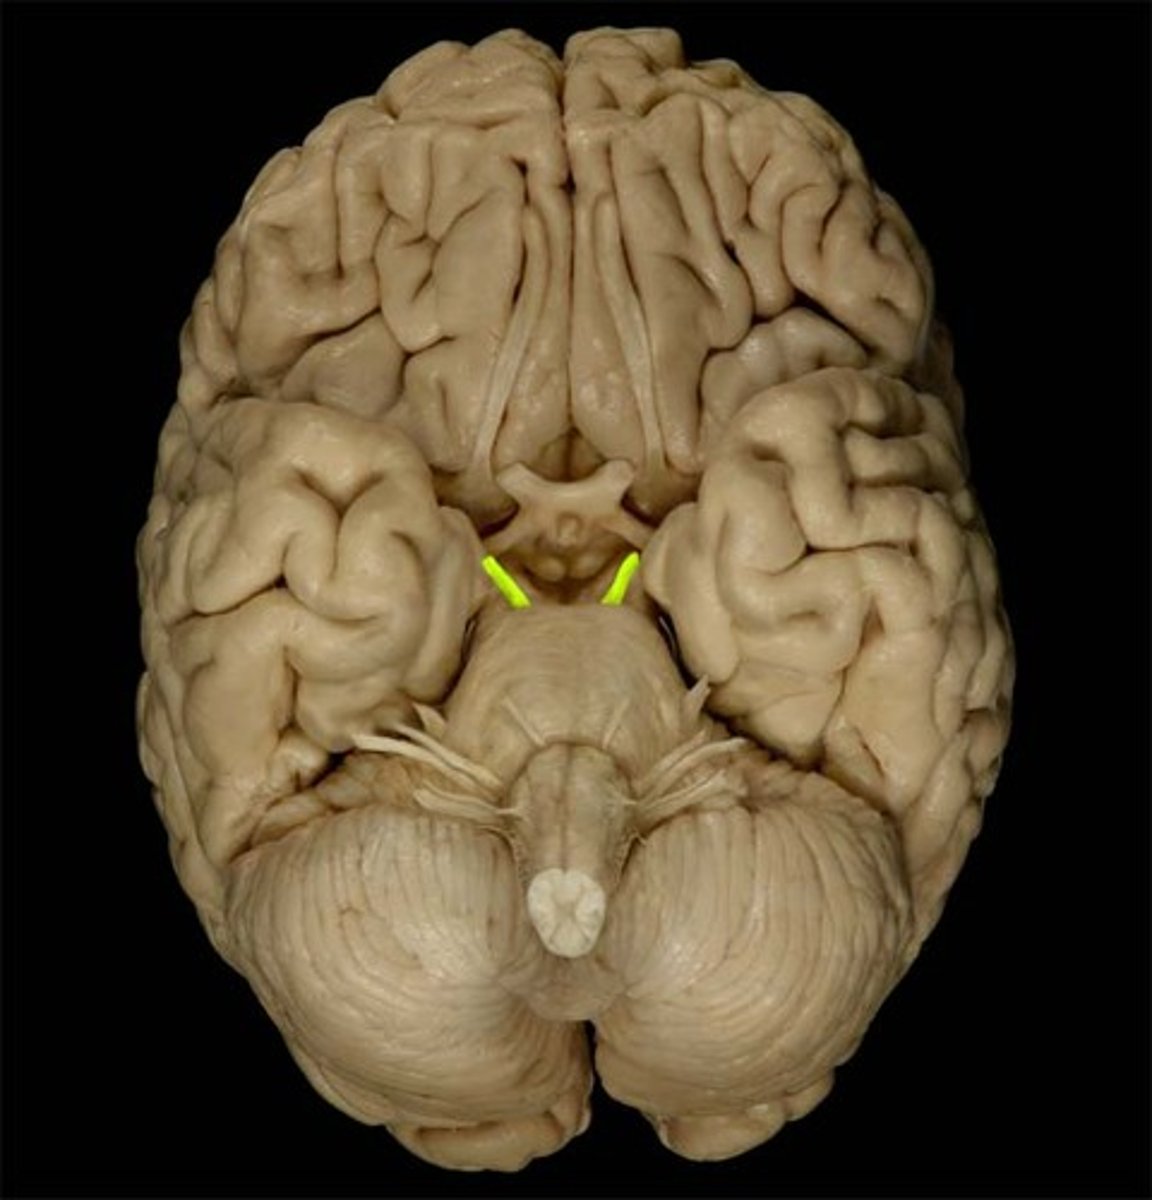

optic nerve (CN II)

Sensory cranial nerve related to vision

optic chiasm

point at which optic nerve fibers cross in the brain

optic tracts

the continuation of the optic nerve fibers beyond the optic chiasma

primary visual cortex

•Located within occipital lobe; receives, processes, stores visual information